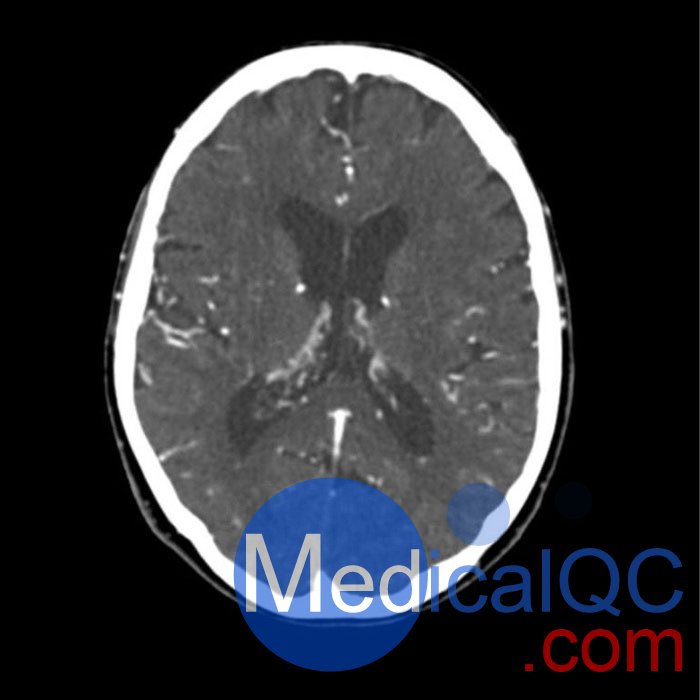

WEK51-02 CT血管造影頭模,WEK51-02 CTA頭部模型模擬動(dòng)脈期造影劑增強(qiáng)頭部(CT 血管造影)。頸部和上胸包括主動(dòng)脈弓和第五胸椎。頂點(diǎn)被包括在內(nèi),直到皮膚水平以下約 0.5 厘米。胸廓模體部分不包括通常不屬于 CTA 檢查的肩部和背部部位。

頸動(dòng)脈內(nèi)動(dòng)脈兩側(cè)鈣化,右側(cè)中度狹窄。否則,模體沒有明顯的血管病變。

該模型可用于 CT(包括 CBCT)以評(píng)估和優(yōu)化 CTA 成像性能和后處理應(yīng)用,例如血管分割,包括支持 AI 的應(yīng)用。它也非常適合培訓(xùn)目的。

該模型提供了對(duì)血管結(jié)構(gòu)、軟組織和骨組織的詳細(xì)和逼真的模擬,包括淋巴結(jié)等小細(xì)節(jié)??障吨刑畛渲s-160的纖維素-聚合物復(fù)合材料。

對(duì)頭頸部血管進(jìn)行逼真的模擬,直至主動(dòng)脈弓、骨骼和軟組織。兩側(cè)頸動(dòng)脈分叉處頸內(nèi)動(dòng)脈鈣化,右側(cè)輕度狹窄。

WEK51-02 CT血管造影頭模,WEK51-02 CTA頭部模型成像效果圖: